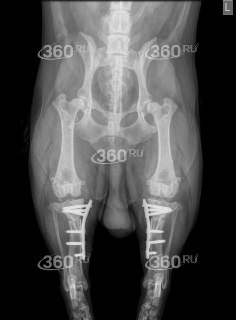

🔥🔥🔥🔥🔥Ветеринары из Петербурга помогли корги «встать на лапы» после тяжелой травмы. Пес по кличке Зевс перестал ходить из-за разрыва связок сразу на обеих задних лапах. Патология делает коленный сустав нестабильным, вызывая острую боль и практически невозможность опираться на конечность.

Врачи провели сложную операцию TPLO — не сшивали связки, а изменили структуру сустава, чтобы вернуть ему устойчивость. Решение оперировать сразу обе лапы помогло ускорить восстановление и избежать повторного наркоза, подчеркнул ветеринарный врач-ортопед Лев Левинсон.